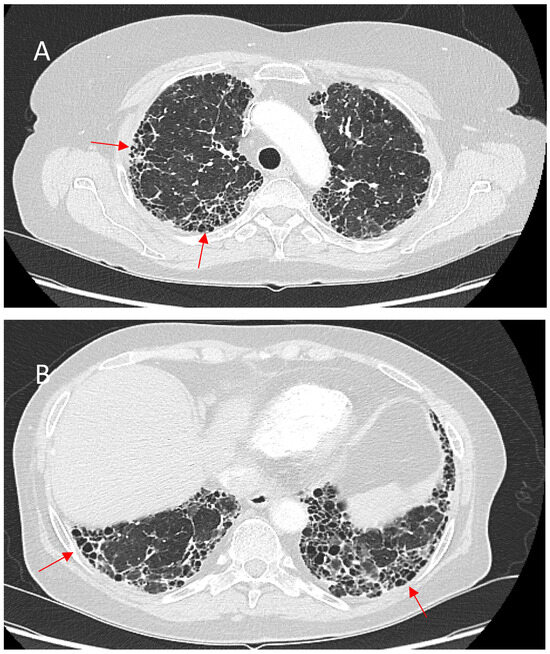

The Role of High-Resolution Lung Computed Tomography to Distinguish Between Fibrosing Hypersensitivity Pneumonitis and Usual Interstitial Pneumonia

Background: Hypersensitivity pneumonitis (HP) is an interstitial lung disease (ILD) caused by repeated exposure to inhaled antigens in susceptible subjects. High-resolution computed tomography (HRCT) of the lungs is the leading diagnostic method for ILDs, but in some cases HRCT findings are not sufficient to distinguish HP and other ILDs, particularly, fibrotic HP (fHP) and usual interstitial pneumonia (UIP). Objective: The aim of this study was to develop HRCT criteria to diagnose fHP in patients with a UIP-like pattern. Methods: In this retrospective study, we analyzed HRCT scans of patients with fHP and a UIP-like pattern who underwent lung biopsy, and patients with idiopathic pulmonary fibrosis (IPF) and a UIP pattern in HRCT. Results: We included 51 patients with confirmed fHP and 24 patients with IPF/UIP in the analysis. IPF/UIP patients were older, were prevalently males, and did not have any systemic autoimmune diseases or risk factors for other ILDs. fHP patients were younger, with an equal number of males and females, and were more likely to be exposed to environmental antigens. HRCT abnormalities in the fHP group predominated in the lower lung areas or were diffuse in axial scans, whereas IPF/UIP patients mostly demonstrated a diffuse craniocaudal distribution and subpleural axial predominance. Centrilobular nodules and mosaic attenuation were present significantly more often in the fHP group; honeycombing, traction bronchiectasis, and emphysema prevailed in IPF/UIP patients. In the logistic regression analysis, patients with fHP and IPF/UIP differed in the presence of centrilobular nodules, honeycombing, and in both craniocaudal and axial distributions of HRCT abnormalities. In the ROC analysis, the combination of centrilobular nodules, honeycombing, and diffuse axial and craniocaudal distributions can predict the diagnosis of fHP (AUC, 0.953 ± 0.022; 95%CI, 0.910–0.995; p < 0.001). Mosaic attenuation and reticulation did not change the probability of fHP. Conclusions: The most significant HRCT features of fHP compared to the UIP pattern were centrilobular nodules, honeycombing, and a diffuse axial and craniocaudal distribution of abnormal findings. Reticulation, mosaic attenuation, and GGO do not increase the probability of fHP. Full article